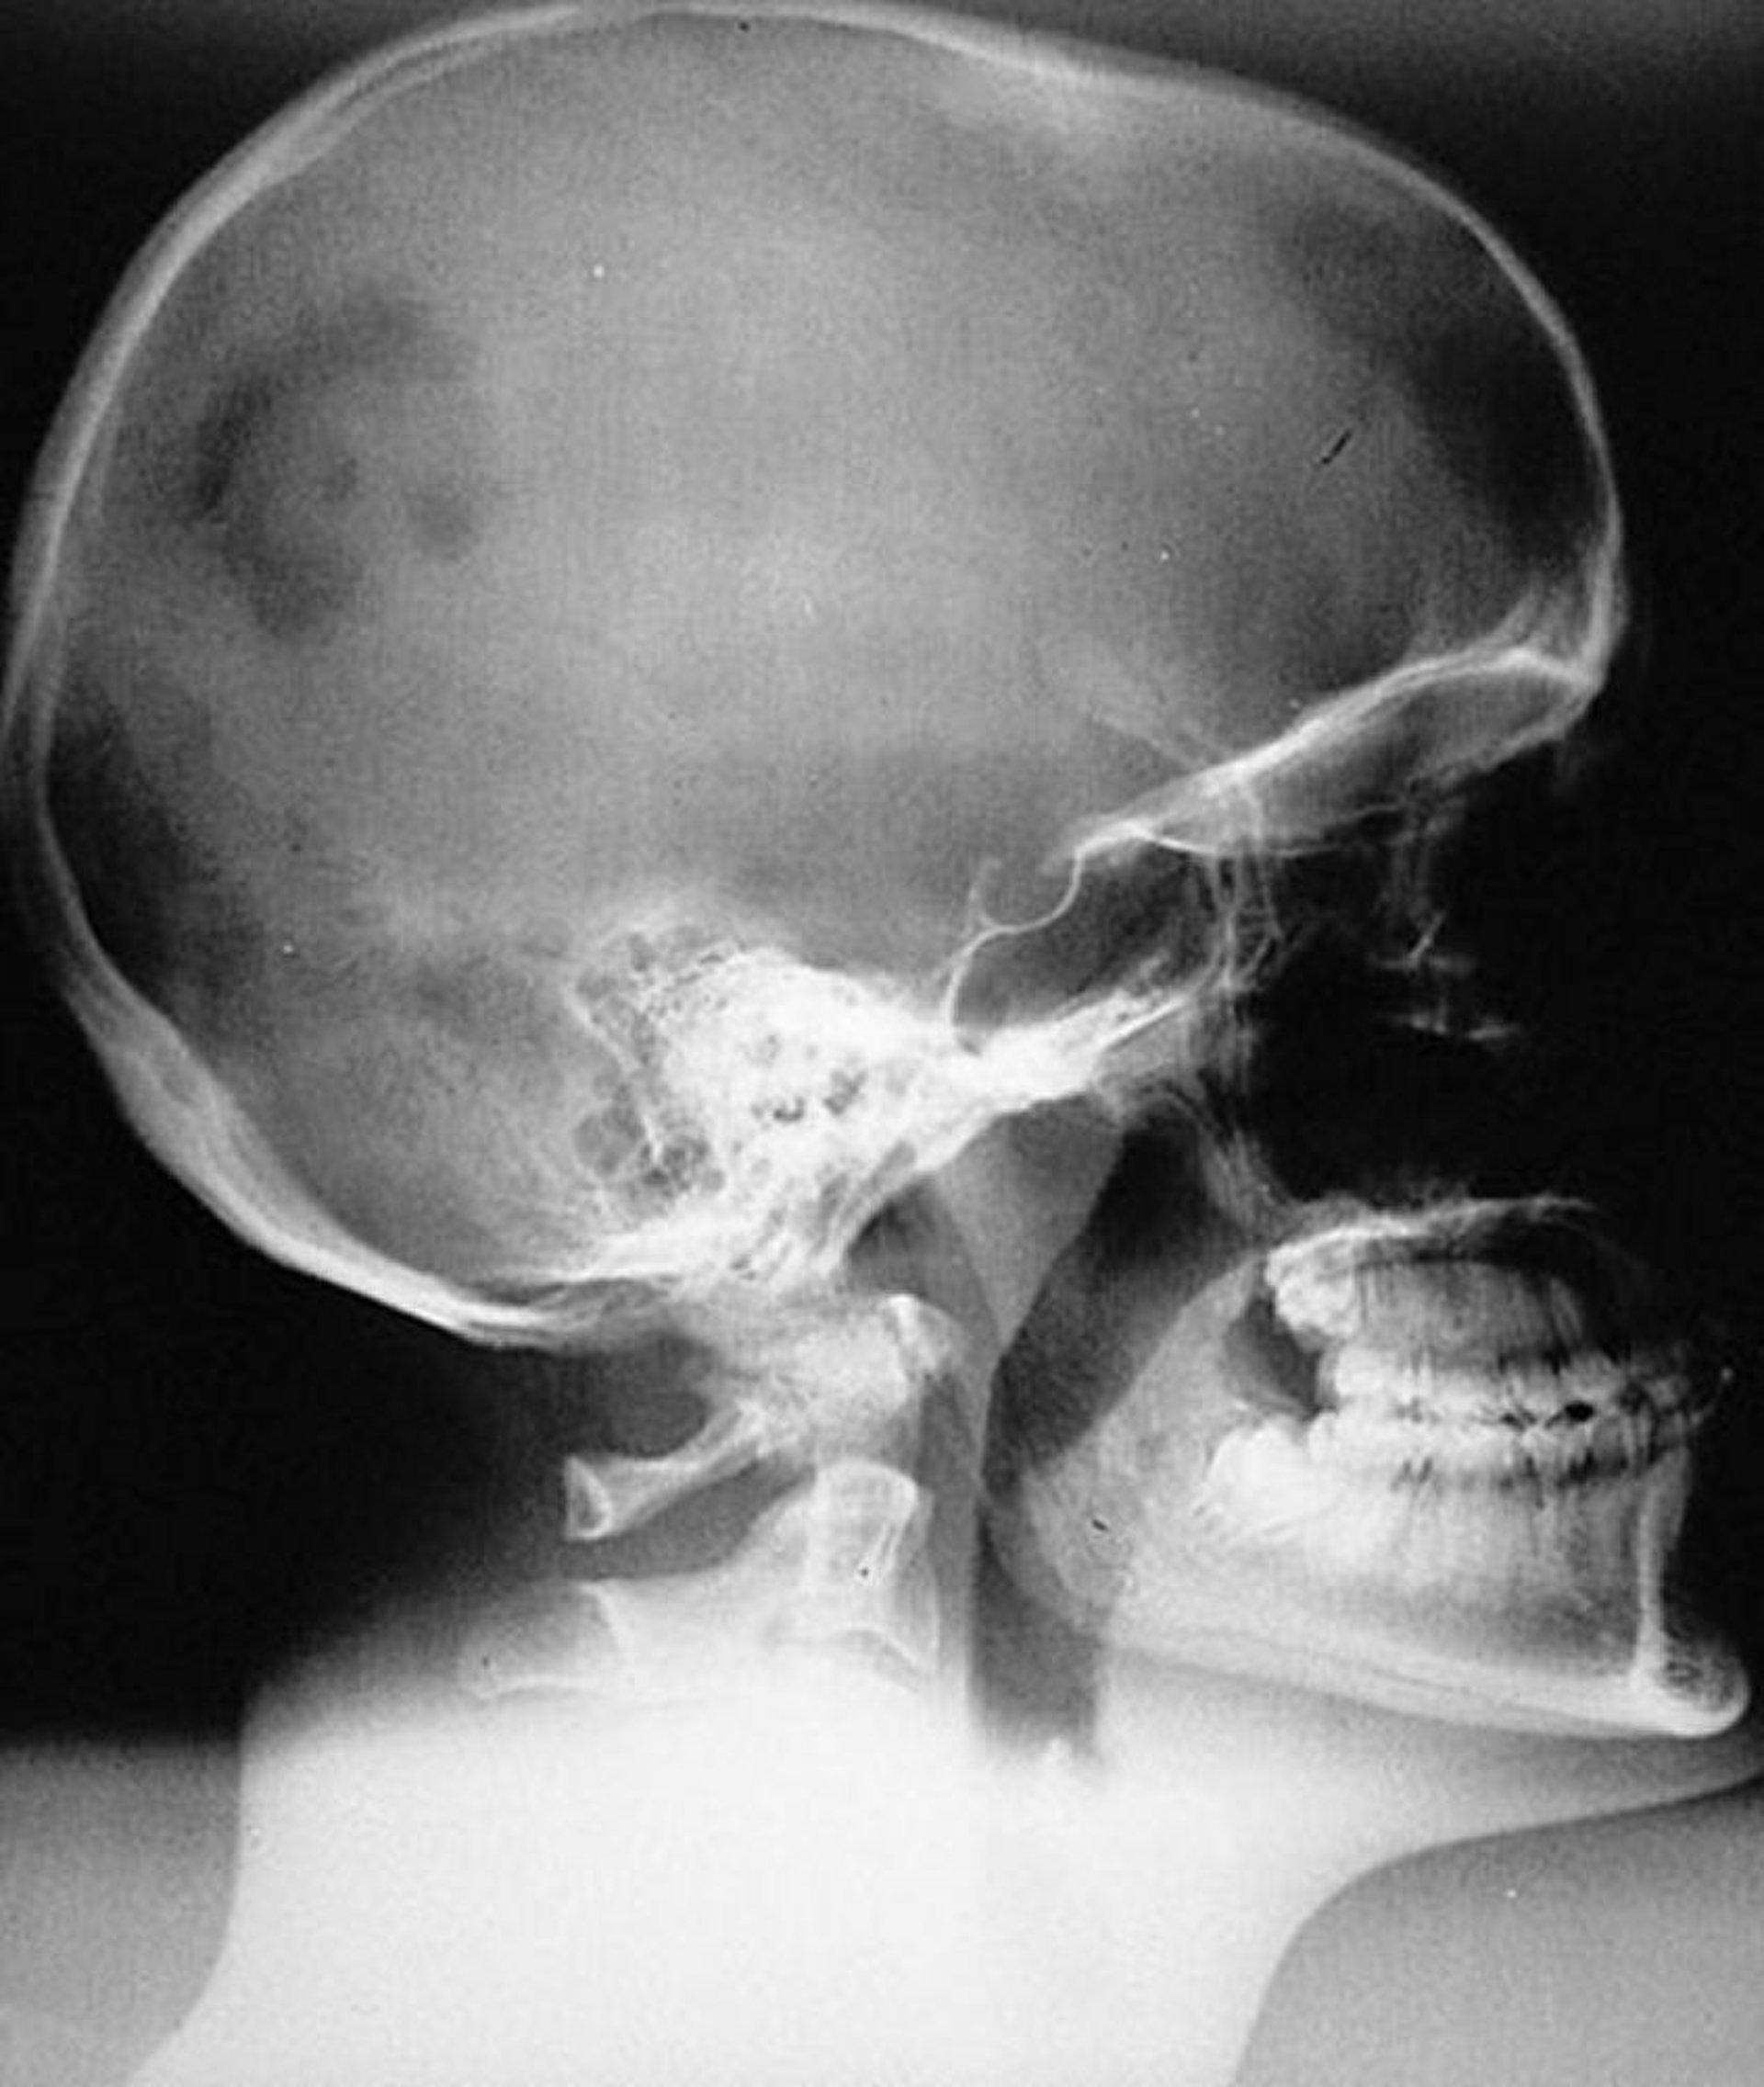

Histiocitose pulmonar de células de Langerhans (Granuloma eosinofílico do crânio)

Aspecto radiográfico de lesão unifocal monostótica típica de HCL (granuloma eosinofílico) do crânio. A lesão é nitidamente marginada, mas não chanfrada.

By permission of the publisher. From Swearingen B, Schaefer P, Primavera J, Klibanski A. In Atlas of Clinical Endocrinology: Neuroendocrinology and Pituitary Disease. Edited by S Korenman (series editor) and ME Molitch. Philadelphia, Current Medicine, 2000.